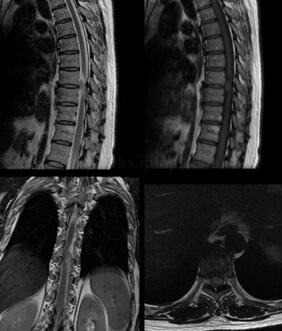

患者女,47岁,自半年前出现腰痛,一个月前出现右下肢麻木,近一周加重,目前行走无力,自诉左手麻木,右下肢渐进性麻木,从足尖开始上行至膝关节,近一周出现整个左腿麻木感,伴发左膝关节麻木。患病来自觉憋尿略有无力感,饮食、睡眠正常(图1)。

图1约平胸8~9椎间盘椎管内左前部髓外硬膜内见卵圆形等T1稍长T2信号影,大小约17.8mm×9.9mm×7.7mm,边界较清,相应脊髓受压向右后方移位。增强扫描病灶均匀明显强化

(胸椎)神经鞘瘤(图2)

图2 瘤细胞梭形,束状排列,局灶呈栅栏状排列,偶见核分裂,未见坏死